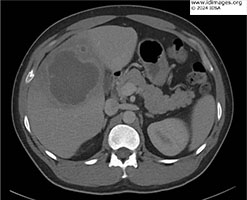

- Initial lab work revealed leukocytosis of 13.6 x103 white blood cells/µL (85% neutrophils, 10% lymphocytes, <1% eosinophils), aspartate transaminase 56 U/L, alanine aminotransferase 60 U/L, alkaline phosphatase 356 U/L and total bilirubin 0.74 mg/dL. Computed Tomography scan of the abdomen with contrast revealed the hepatic abscess (Figure 1).

- Figure 1a: Axial image of Computed Tomography of the abdomen with contrast demonstrating an 8.2 cm abscess in the right lobe of the liver.